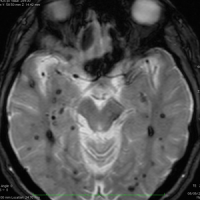

多発性海綿状血管腫 multiple cavernous hemangioma

家族性海綿状血管腫 familial cavernous hemangioma

この様な無数の海綿状血管腫を見ることがあります。多くの場合は家族性(遺伝性)の海綿状血管腫です。200個を超える海綿状血管腫があっても普通に何の障害もなく暮らしている患者さんもいます。脊髄の中にも発生しますから,脊髄のMRIもしていただきましょう。

小さな多発性の海綿状血管腫は,T2*(ティーツースター)という左の画像では見えるのですが,右にあるような普通のT1強調画像というのでははっきりみえません。

左上のT2*でみられるように多発性海綿状血管腫の成人男性に発生した中脳海綿状血管腫です。複視と歩行失調で発症して,数回の脳幹部出血を繰り返し,水頭症になったために第3脳室開窓術がなされました。それでも出血は止まらず、両側の動眼神経麻痺による両側眼瞼下垂,歩行失調,嚥下障害などさまざまな中脳症状が進行しました。

しかたがないので手術で摘出しました。なんとか眼瞼が持ち上がるようになり歩行も可能で嚥下もできます。幸いだったのは感覚路(脊髄視床路)の障害による体性疼痛が生じなかったことです。